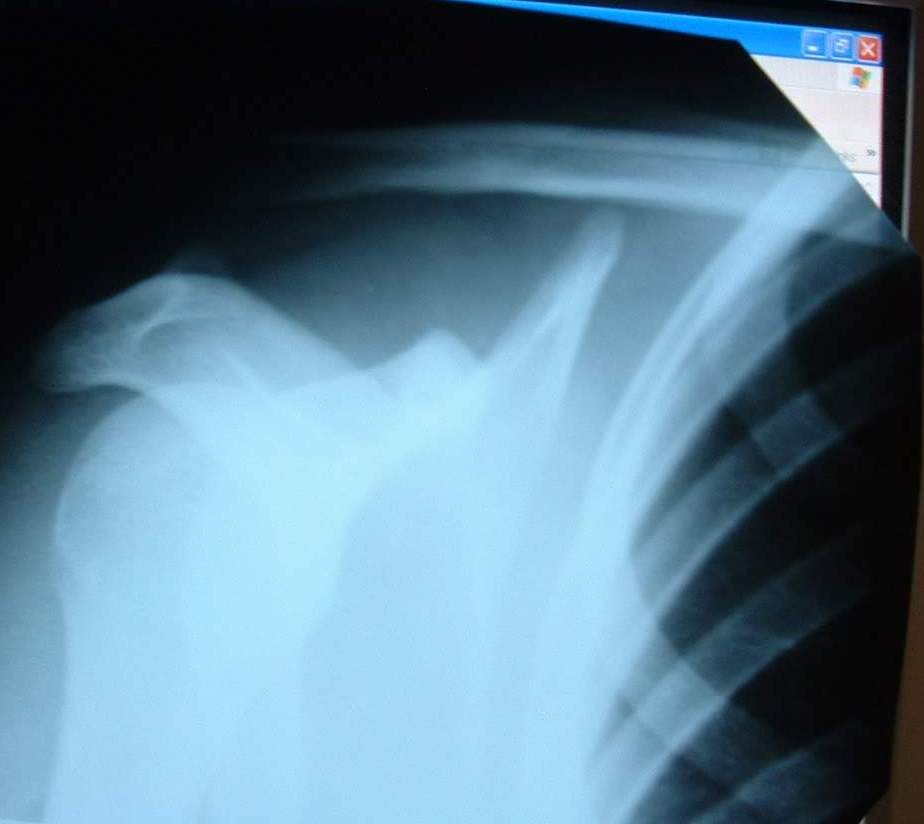

Вот снимок. Все врачи говорят, что операция обязательно. Но их мнения расходятся насчет выбора операции - одни советуют эту hook plate (да, судя по тому, что я видел в отделении травмотологии и изображениям этой пластины в интернете, это она), другие (НИИ ТО Новосибирска) говорят, что лучше лавсана еще ничего не придумано. С применением этих лавсановых нитей обещают 10-12 недель находиться в загипсованом состоянии. При этом аргументация против hook plate - стеснение движения, а также отсутствие эффекта восстановления связок. Я в растерянности, не знаю что делать. Учитывая цены, скорее всего останавлюсь на варианте без hook plate. Непонятно почему, тут либо вообще не делают операций с ними (то же НИИ ТО), либо делают с дорогими швейцарскими. Можете прокомментировать операцию с лавсановыми нитями (преимущества и недостатки относительно других методов) ? Как бы вы посоветовали поступить пациенту с таким диагнозом?

Снимок1.JPG

31KB (32439 bytes)